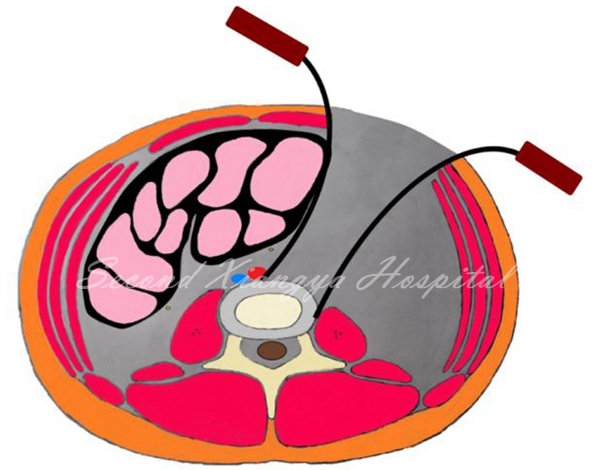

4.L4/5及以上节段,用常规腹部拉钩将将腹主动脉和静脉向内侧牵开,但不用过中线;

血管拉开示意图

5.另一拉钩置于椎体侧前、交感神经链前方,将其稍向后牵开;

拉钩示意图